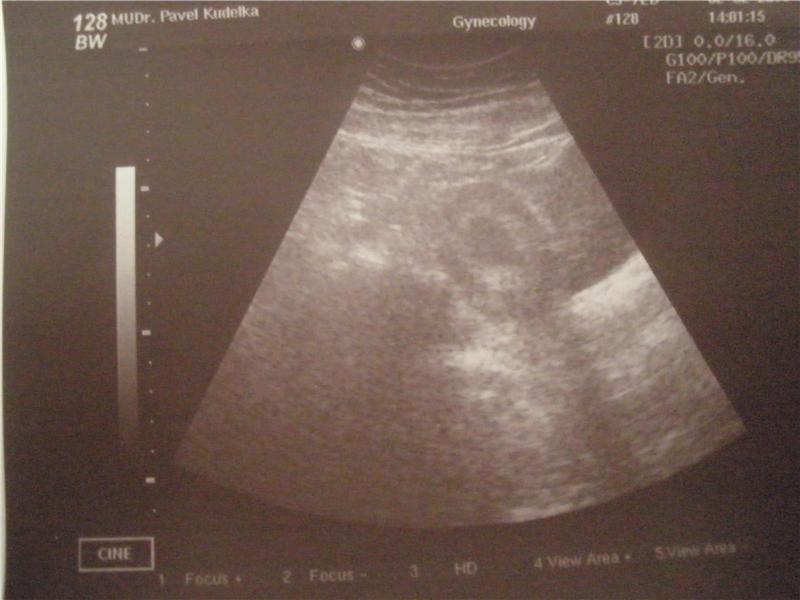

naše mimi v 7.týdnu